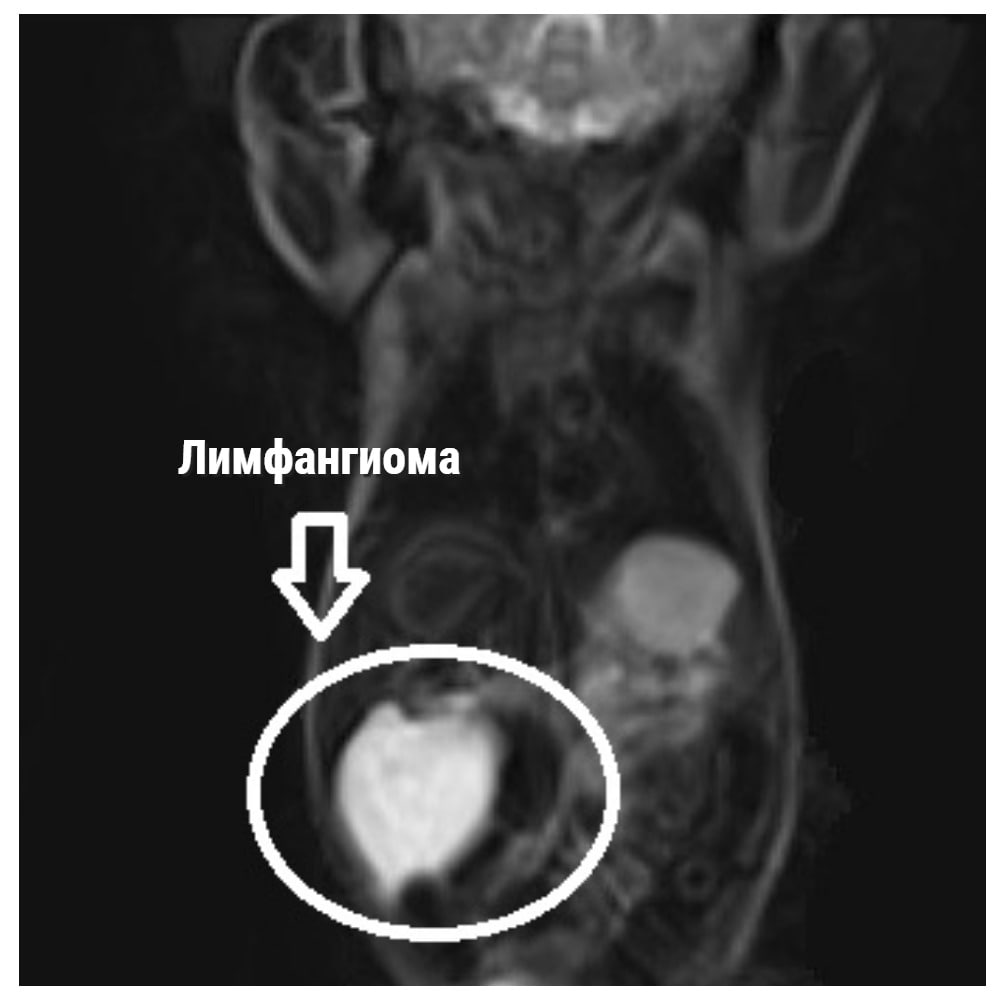

«После рождения состояние ребенка было стабильным, началось дообследование: УЗИ, МРТ. По данным УЗИ, в проекции правой доли печени визуализировалось образование неправильной округлой формы, с неровными, но достаточно четкими контурами, многокамерное, размером почти 6 на 3 см», - сказал заведующий отделением хирургии новорожденных Михаил Рехвиашвили.

«На 7 сутки жизни проведено радикальное хирургическое удаление образования. Было выявлено, что образование представлено одной кистой, сообщающейся с более мелкой кистой. Визуально образование соответствовало лимфангиоме печени – доброкачественному образованию, что подтвердили последующие исследования. Проведено радикальное удаление образования в пределах здоровых тканей. Операция проводилась полностью лапароскопически – через мини-проколы передней брюшной стенки. После операции разрезы практически не заметны», - добавил Рехвиашвили.